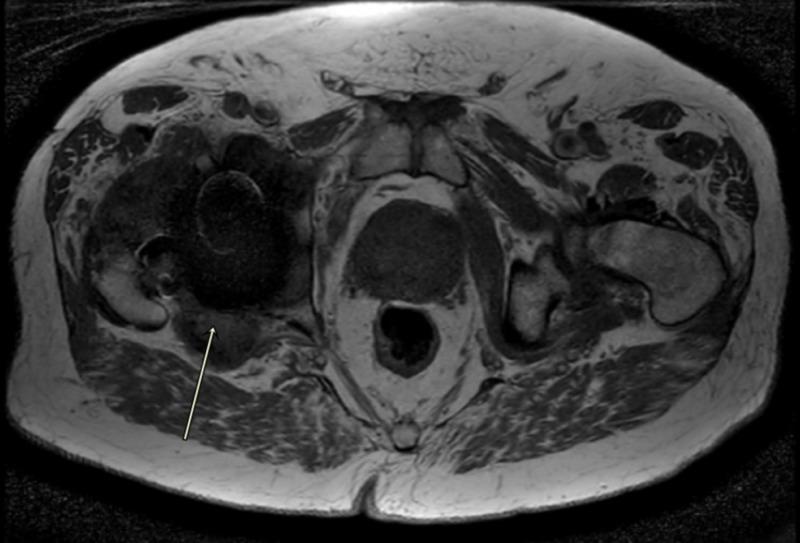

Trunnionosis is a type of corrosion and wear at the head-neck taper junction of the femoral implant, and it can be a slow and silent catastrophe. Simultaneous prosthetic joint infection (PJI) is occasionally possible based on the fulfillment of a few of the minor criteria from the Musculoskeletal Infection Society (MSIS), but the existing literature lacks adequate evidence to support that the infection actually exists. We are presenting a case of an 82-year-old man with right total hip arthroplasty performed over a decade prior to presenting to the emergency room with a sudden-onset pop followed by groin pain and difficulty in walking. Radiographs showed a dissociated femoral implant at the level of trunnion with malalignment and heterotopic ossification. Metal Artifact Reduction Sequence MRI of the right hip showed mixed type-two and type-three pseudotumors, and atrophy of surrounding abductor muscles. The erythrocyte sedimentation rate was within normal limits, C-reactive protein was borderline raised, and serum cobalt-chromium levels were elevated without any signs of systemic metal toxicity. Hip joint aspirate revealed blood-stained fluid flooded with red blood cells, leukocytes and neutrophils, and a positive alpha-defensin assay. These findings were interpreted as positive for prosthetic joint infection. Intraoperatively, there was severe wear of the inferomedial aspect of the femoral head-neck junction and extensive metallosis throughout the right hip. Tissue and fluid specimens were sent for cultures, sensitivities, and histopathology for pseudotumor and infection evaluation. An articulating antibiotic spacer was then placed with the intent to perform a staged reconstruction of the femur and right acetabulum. Final synovial, bone, and soft tissue cultures, as well as histopathological photomicrograph of the tissue slides, were negative for infection. This case demonstrates the striking features of metallosis associated with trunnion failure of a metal-on-polyethylene total hip joint prosthesis that was simultaneously showing signs of prosthetic infection by satisfying the minor criteria according to the latest guidelines by the MSIS with a strikingly high cell count of red blood cells in the synovial fluid exam, indicating inflamed hyper-vascular pseudotumors vs. hemarthrosis vs. bloody tap. Diagnostic dilemma led by positive synovial fluid alpha defensin, high synovial neutrophil and white cell count results with negative final cultures or infection on histological slides raises concern that infection was not present and two-stage revision arthroplasty with six weeks of antibiotics was not necessary along with increased risk of morbidity, mortality as well as cost of care.

股骨柄腐蚀是指股骨植入物头颈锥度交界处的一种腐蚀和磨损情况,它可能是一场缓慢且悄无声息的灾难。根据肌肉骨骼感染学会(MSIS)的一些次要标准,偶尔可能会同时发生人工关节感染(PJI),但现有文献缺乏足够证据支持感染实际存在。我们报告一例82岁男性患者,该患者在十多年前接受了右全髋关节置换术,之后因突然出现的砰的一声响,随后出现腹股沟疼痛和行走困难而前往急诊室就诊。X线片显示股骨柄水平处股骨植入物分离,伴有排列不齐和异位骨化。右髋关节的金属伪影减少序列MRI显示为混合型二型和三型假肿瘤,以及周围外展肌萎缩。红细胞沉降率在正常范围内,C反应蛋白略升高,血清钴铬水平升高,但无任何全身金属中毒迹象。髋关节穿刺抽出的液体为血性,充满红细胞、白细胞和中性粒细胞,α-防御素检测呈阳性。这些结果被解释为人工关节感染呈阳性。术中发现股骨头颈交界处的内下侧严重磨损,整个右髋关节有广泛的金属沉着症。将组织和液体标本送去进行培养、药敏试验以及用于假肿瘤和感染评估的组织病理学检查。然后放置了一个可活动的抗生素间隔物,打算分阶段重建股骨和右髋臼。最终的滑膜、骨和软组织培养结果,以及组织切片的组织病理学显微照片显示感染为阴性。该病例展示了与金属对聚乙烯全髋关节假体股骨柄失效相关的金属沉着症的显著特征,根据MSIS的最新指南,该病例同时通过满足次要标准显示出人工感染的迹象,在滑膜液检查中红细胞计数极高,提示为炎症性高血管假肿瘤与关节积血与血性穿刺的区别。滑膜液α-防御素阳性、滑膜中性粒细胞和白细胞计数高且最终培养结果或组织学切片感染为阴性所导致的诊断困境,引发了人们对感染是否存在的担忧,以及六周抗生素治疗的两阶段翻修关节成形术是否必要,同时还增加了发病、死亡风险以及护理成本。